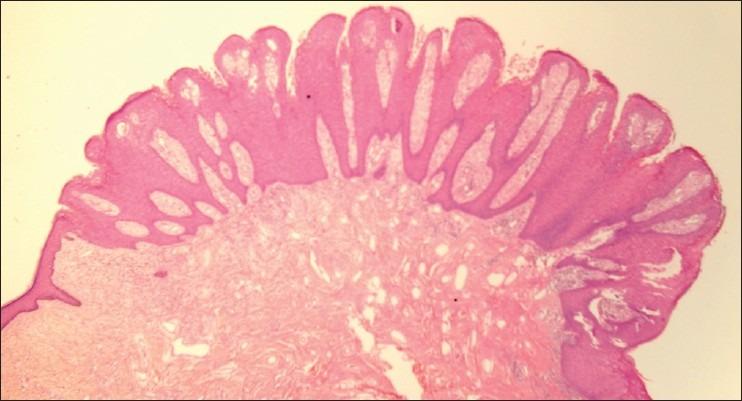

We describe five cases of verruciform xanthoma (VX). The patients, all males, presented with single warty verrucous lesions of 0.5-2 cm size that had been diagnosed clinically as viral warts (four cases) and leukoplakia (one case). Two patients had the lesion in the oral cavity, two on the genital mucosa, and one on the scrotal skin. Histopathology was diagnostic, with verrucous and papillomatous epidermal hyperplasia with the silhouette of a viral wart but with numerous foamy histiocytes packed in the elongated dermal papillae. Columns of deep parakeratosis and neutrophils in the upper spinous layers, with a dermal plasma cell infiltrate were the other histopathologic findings. Excision of the lesions was curative, without recurrences, in the two patients who had lesions in the oral cavity; follow-up was not available in the cases with genital lesions. VX is an uncommon but distinctive clinicopathologic entity affecting the oral and genital mucosa that may be mistaken for benign, premalignant, and malignant conditions. VX can be diagnosed with certainty only on histopathologic examination.

我们描述了5例疣状黄瘤(VX)。患者均为男性,表现为大小为0.5 - 2厘米的单个疣状、乳头状病变,临床诊断为病毒疣(4例)和白斑(1例)。2例患者病变位于口腔,2例位于生殖器黏膜,1例位于阴囊皮肤。组织病理学检查具有诊断意义,表现为疣状和乳头状表皮增生,形似病毒疣,但在拉长的真皮乳头中有大量泡沫状组织细胞。深层角化不全柱和棘层上部的中性粒细胞,以及真皮浆细胞浸润是其他组织病理学表现。对2例口腔病变患者进行病变切除后治愈,无复发;生殖器病变患者未进行随访。VX是一种罕见但独特的临床病理实体,可累及口腔和生殖器黏膜,可能被误诊为良性、癌前和恶性病变。VX只有通过组织病理学检查才能确诊。